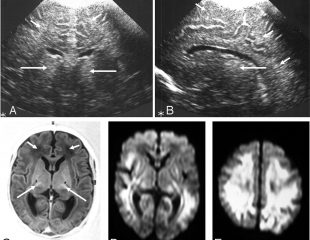

سونوگرافی جمجمه ای از امواج صوتی منعکس شده برای ایجاد تصاویری از مغز و فضاهای مایع داخلی (بطن) که مایع ...

اولتراسوند جمجمه ای از امواج صوت منعکس شده برای ایجاد تصاویر مغز و فضاهای مایع داخلی (بطن) که از طریق ...